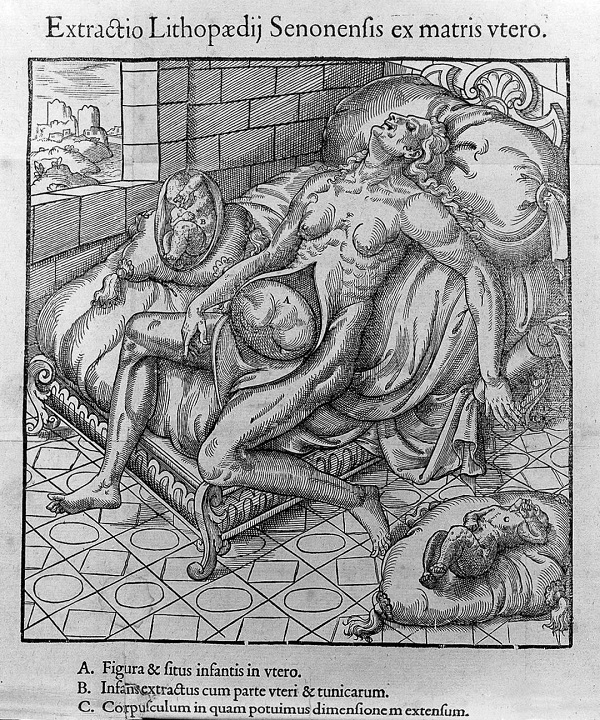

外科医生纪录的桑斯胎儿的形象

在这之后,其中一名外科医生,便保留这了具女婴尸体。

他将此写成医学报道,并将女婴多次展览,最后卖给了商人。

在那个剖腹产与超声波未出现的时代,这个长期怀孕的故事就不断被提起。

所以这桑斯怪胎,也因此出了名。

许多人都会慕名而来,就为了看她一眼。

外科医生纪录的桑斯怪胎